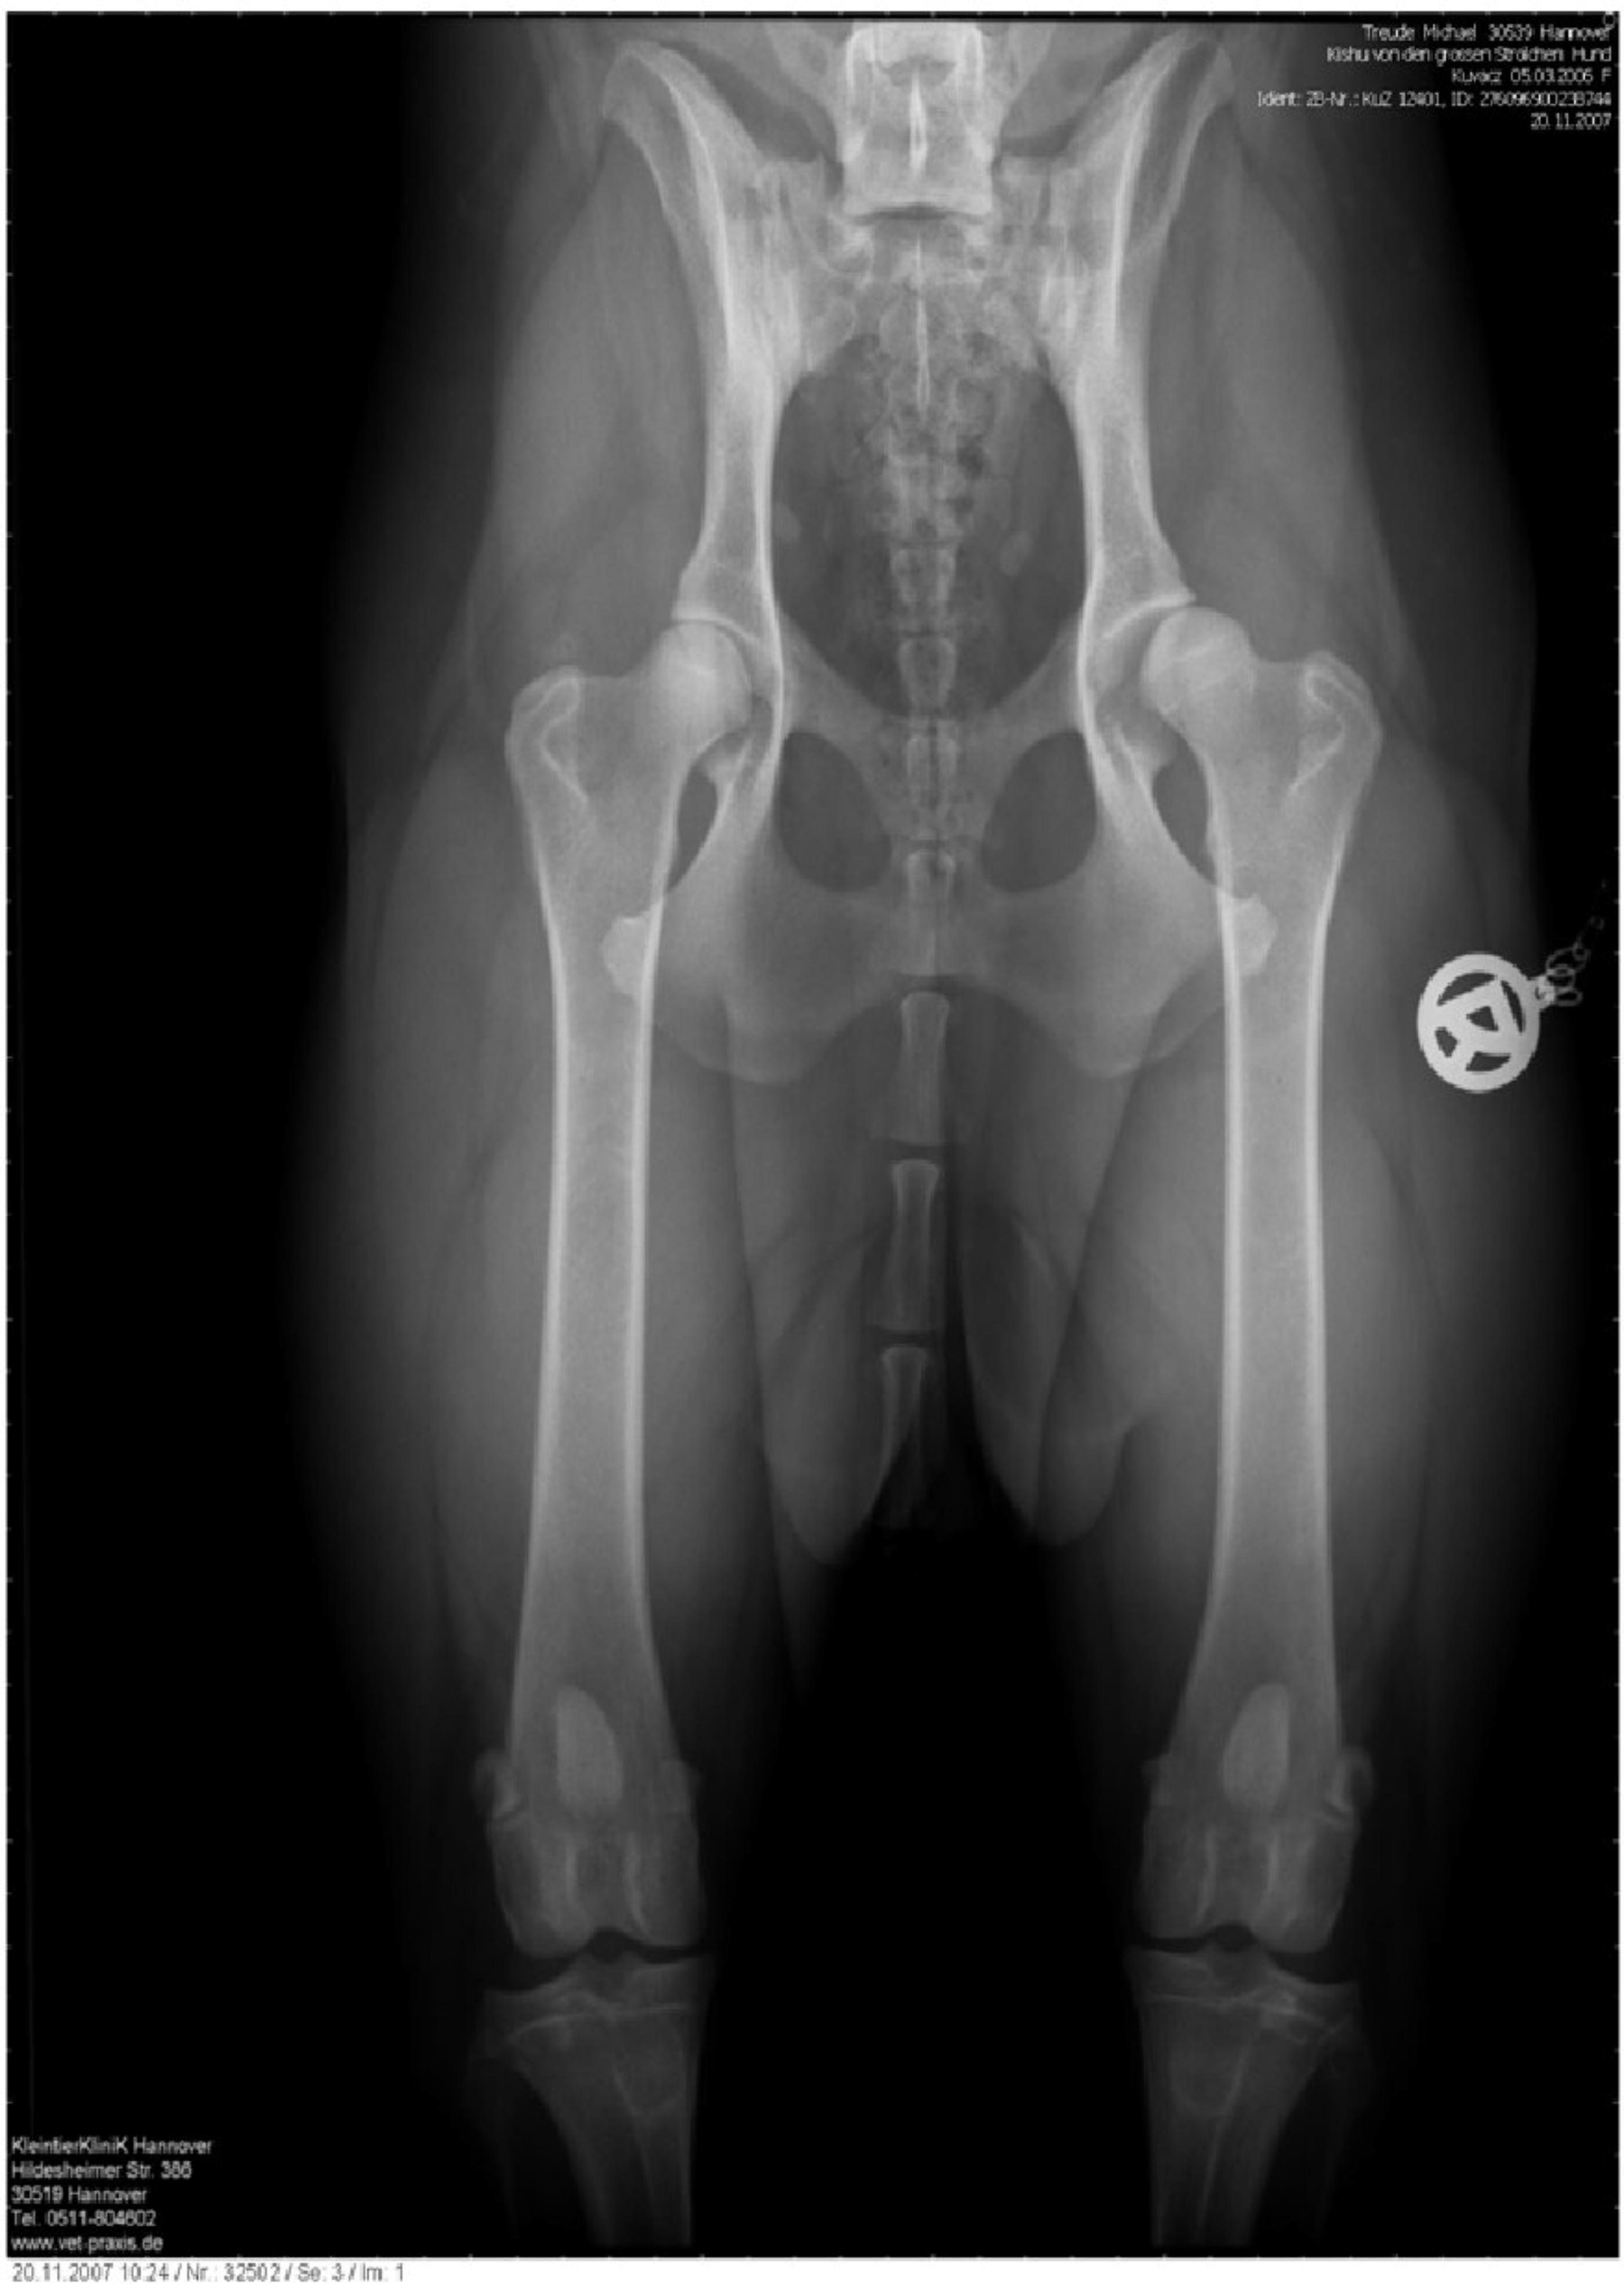

Wie geht es weiter? Kishu bekommt jetzt zusätzlich Ergänzungsnahrung wie z. B. CANOSAN um eine Verschlechterung ihres derzeitigen Top Zustandes möglich lange raus zu zögern bzw. ganz zu verhindern. Bis jetzt hat sie keinerlei Probleme mit ihrem Skelett, deshalb besuchen wir auch regelmäßig Ausstellungen, um immer wieder unterschiedliche Urteile über ihr Gangwerk zu erhalten. Denn die Richter der Ausstellungen haben meistens ein gutes Auge für einen "unrunden" Lauf eines Hundes. Michael Treude - 2008/08 HD - Röntgenaufnahme